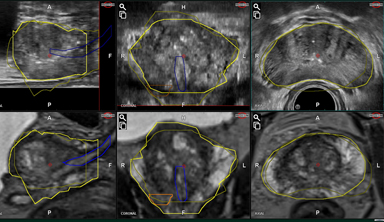

Overlap of US & MRI

prostate contouring

Automatic Elastic Fusion

Adopt mode

(manual adjustment)

Automated Contour Tracking

(real-time tracking with Prostate movements)